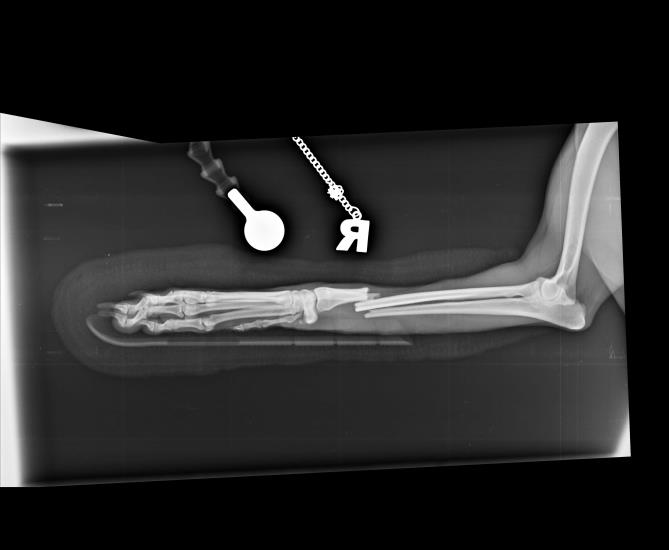

A 1-year-old female Whippet presented with a distal diaphyseal, simple, transverse, closed radius and ulna fracture.

The radiograph below shows the repair with two locking compression plates.